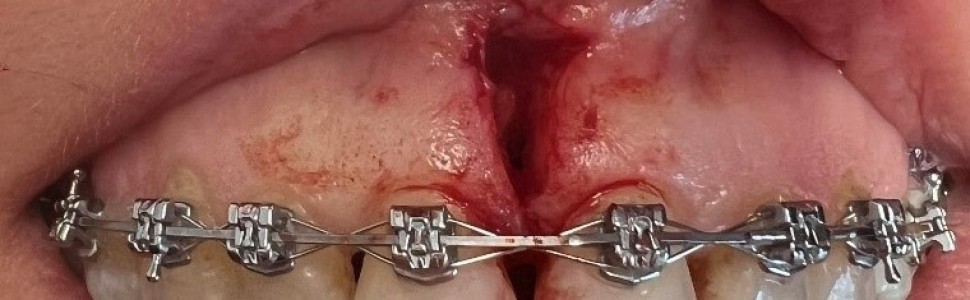

Ryc. 1. Korekta przyczepu wędzidełka wargi laserem CO2. A. przed zabiegiem; B. po zabiegu.

Ryc. 2. Korekta przyczepu wędzidełka wargi laserem CO2. A. przed zabiegiem; B. po zabiegu.

Ryc. 3. Wycięcie wędzidełka wargi skalpelem A. bezpośrednio po wycięciu; B po założeniu szwów.